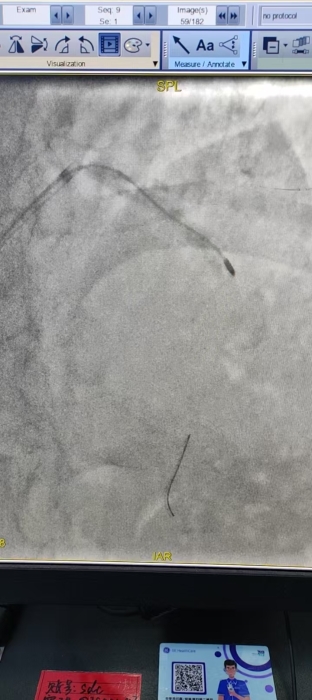

手术过程中,张家立主任团队凭借精湛的操作技术,顺利完成钙化病变旋磨修饰、震波球囊预处理及支架精准植入。

△术后